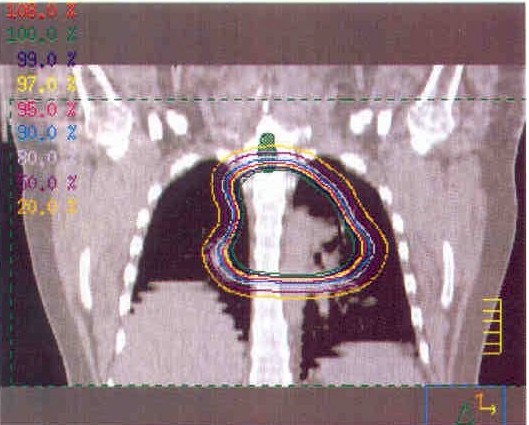

these are CT scan pictures and x-rays shoing the location of my tumor, it's current size, and the area that will be getting radiation therapy...

tumor3.jpg (64917 bytes)